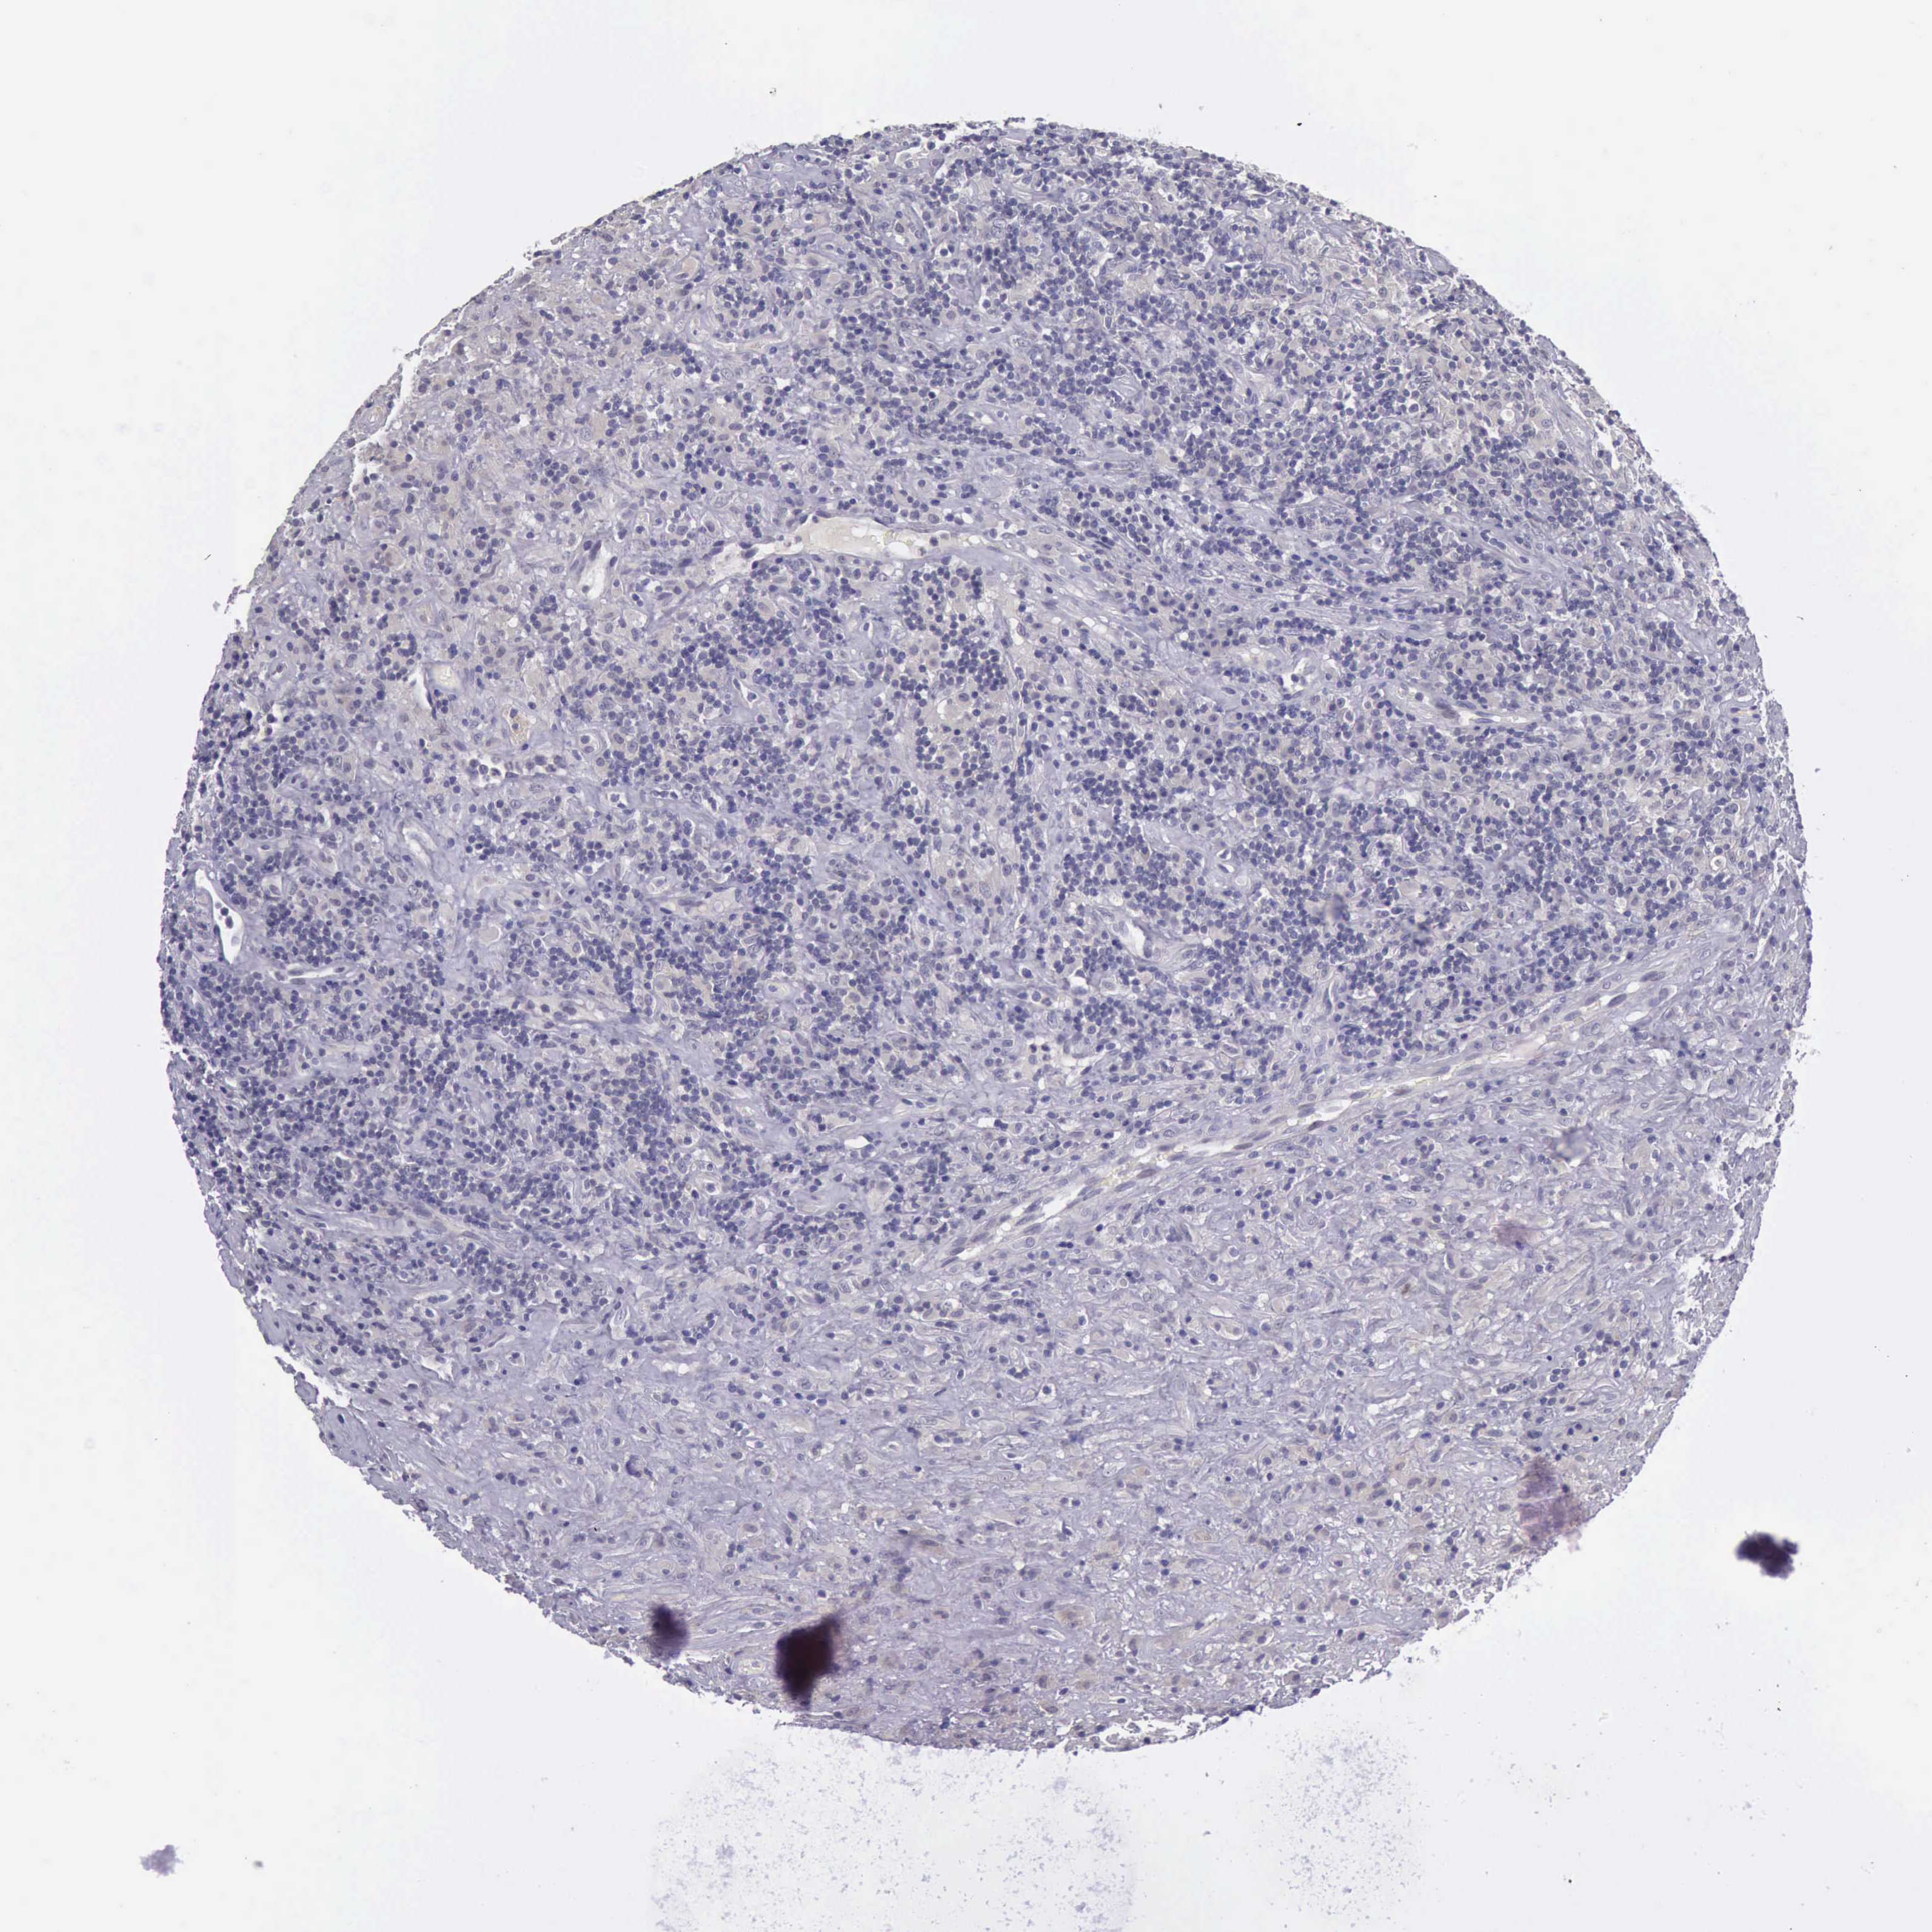

LYMPHOMA - Protein expressioni

A mouse-over function shows sample information and annotation data. Click on an image to view it in a full screen mode. Samples can be filtered based on level of antibody staining by selecting one or several of the following categories: high, medium, low and not detected. The assay and annotation is described here.

Antibody stainingi

Antibody staining in the annotated cell types in the current human tissue is reported as not detected, low, medium, or high, based on conventional immunohistochemistry profiling in selected tissues. This score is based on the combination of the staining intensity and fraction of stained cells.

Each image is clickable and will lead to virtual microscopy that enables deeper exploration of all samples and also displays staining intensity scores, fraction scores and subcellular localization as well as patient and tissue information for each sample.

Antibody HPA001056

Antibody CAB005081

Malignant lymphoma, non-Hodgkin's type, High grade

Hodgkin's disease, NOS

Malignant lymphoma, non-Hodgkin's type, Low grade